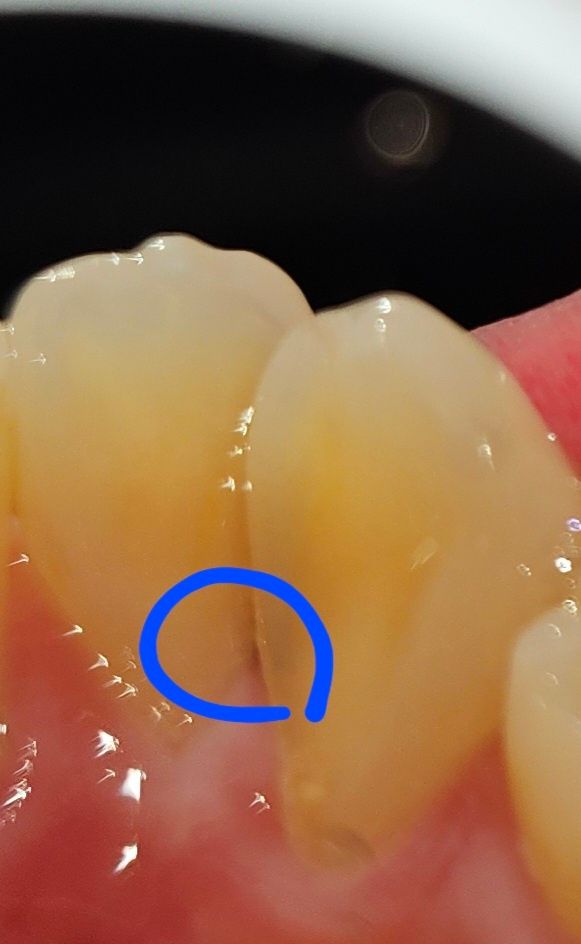

이거 인접면 충치인가요? 궁금해요(사진o)

2~3일전부터 갑자기 보이기 시작했는데 치실을 해봐도 안없어지고 살짝 검은색 줄로 보이는데 사진으로보는것보다 실제로 보면 좀 더 검은색으로 치아가 닿는면에 긴 검은색 줄이 있습니다..

2달전에 엑스레이 찍었을때에 충치가 따로 안보인다고 했는데 인접면 충치일까요??

충치가 있는 것으로 보입니다. 치과에 내원하셔서 정확한 검진을 받아보시는 것이 좋겠습니다.

사진으로만은 정확하게 판단하기 힘들어 보입니다.

인접면에 착색이 되었을수도 있고 충치일수도 있기 때문에 치과에서 자세한 확인을 하는것이 좋습니다.

육안상으로 보면 충치같긴합니다. 작은 엑스레이를 찍어서 한번더 정확히 확인해보시는게 좋을것같습니다.

치아가 총생(겹쳐있음)이 있기 때문에 방사선 사진 상에는 잘 보이지 않을 수 있습니다

사진상 봤을때 초기충치의 가능성도 있어보입니다

다만 해당부위는 원래 충치가 잘 생기는 부위는 아니고 치료도 쉽지 않습니다

일단 찬것에 통증이 없다면 적극적으로 치료를 하기보다는 지켜볼 정도로 생각됩니다

현재 착색으로 인한 변색일 가능성도 있기에 우선은 정확한 상태 확인을 위해서는 치과에 방문하여 진료를 받길 권합니다.